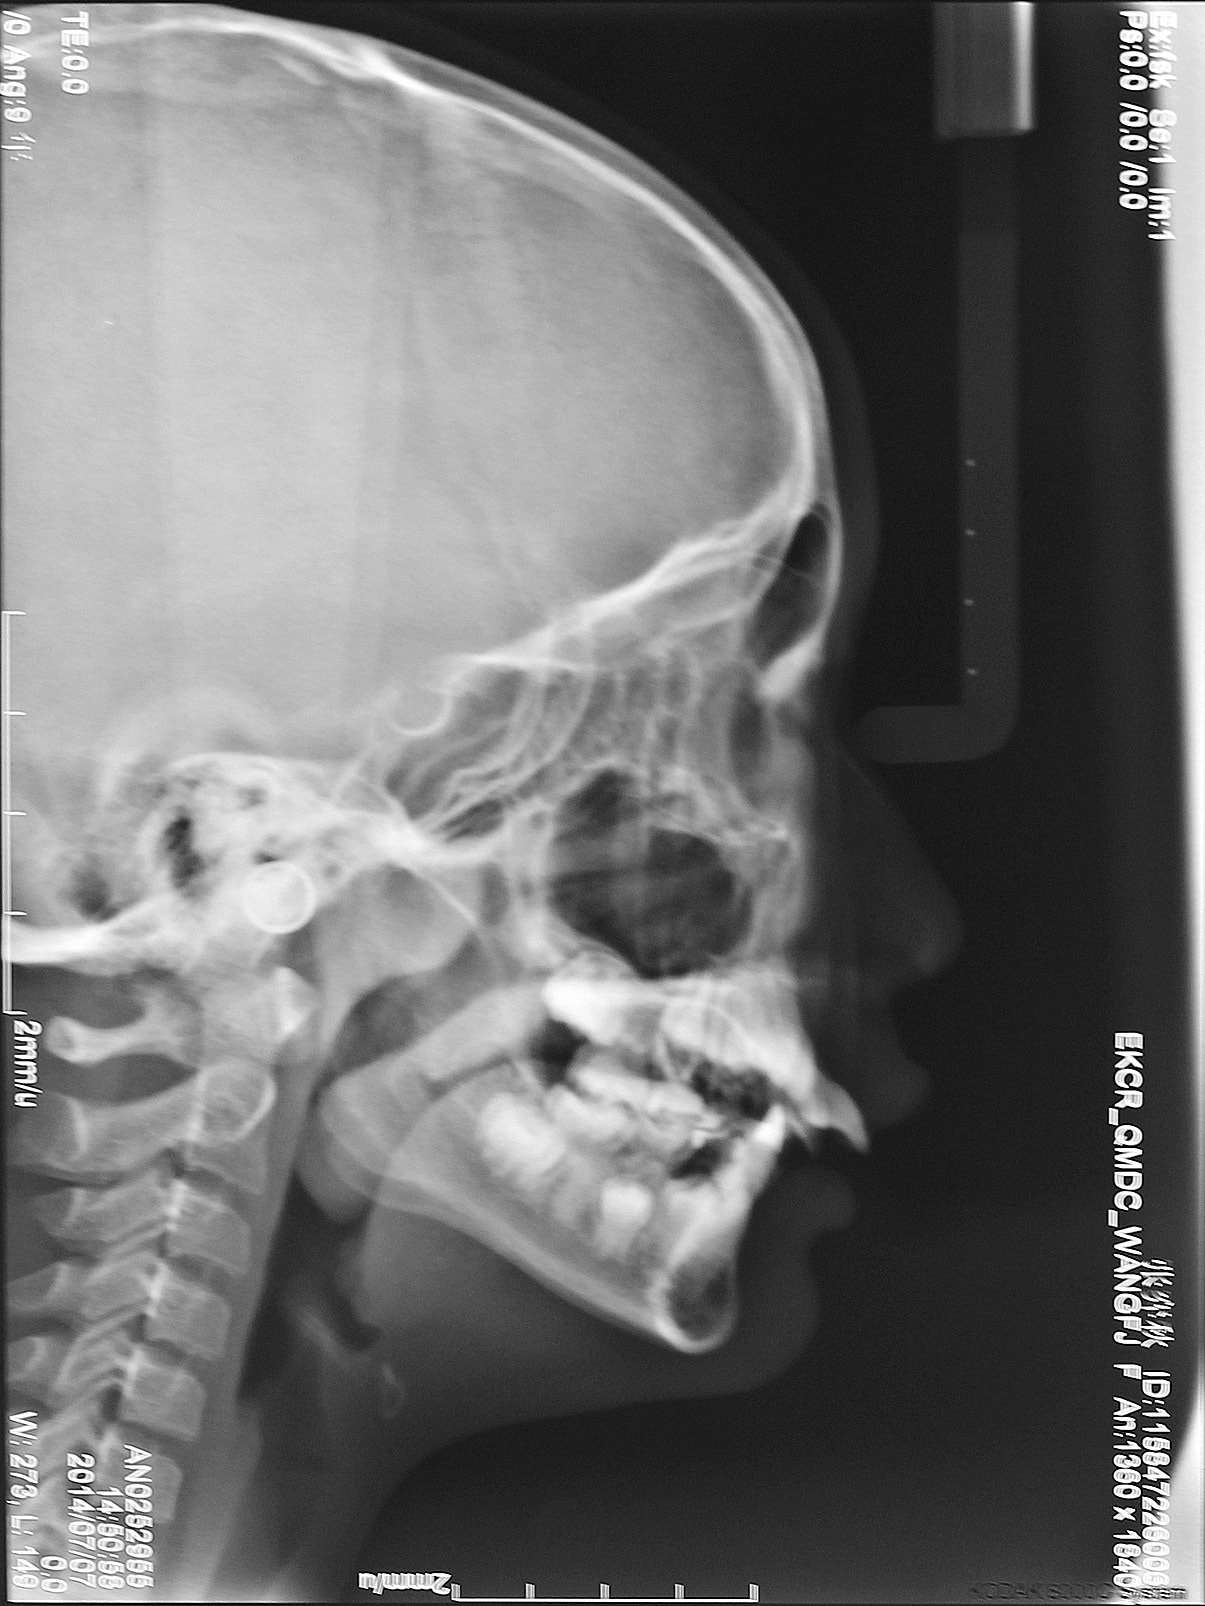

Baccetti等发现,从青春期晚期至成年早期,Ⅱ类 1 分类患者颅面部骨骼因为生长发育所带来的变化较小 [19] 。Jacob和Buschang认为,与Ⅰ类人群相比,Ⅱ类 1 分类患者的下颌骨更为后缩,下颌骨的生长量较小,但男性的下颌骨生长量多于女性 [20] (图 2-7)。

图 2-7 在 10~15 岁之间,Ⅱ类 1 分类患者和Ⅰ类人群的下颌骨垂直向和水平向的生长改变图中显示 10 岁时,下颌骨的初始位置位于“0”点(X轴和Y轴)(摘自Helder B. Jacob and Peter H. Buschang [20] )